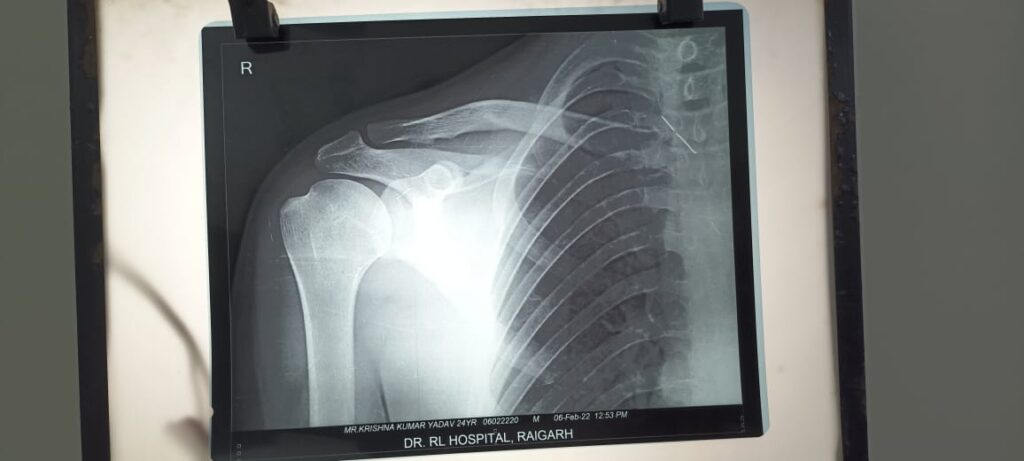

.24 वर्षीय युवक (नाम न छापने के शर्त पर )जिसका कंधा बार – बार उतर जाता था l युवक का कंधा लगभग 10से 15 बार उतर चूका था l जिसके कारण उसे असहनीय पीड़ा होती थी l व उसे खेलने कूदने काम करने तैराकी करने मे हमेशा डर बना रहता था l कई जगह इलाज कराने के पश्चात् डॉ. आर. हॉस्पिटल मे डॉ प्रशांत से मिलकर अपनी बीमारी के बारे मे बताया जाँच पश्चात् पता चला की युवक का शोल्डर डिसलोकेशन ( कंधे का उतर जाना ) हो

गया हैं । क्या कहते हैं डॉक्टर इस सम्बन्ध मे डॉ. प्रशांत ने बताया की युवक का कंधा बार बार उतर जाता हैं l जिसे उन्होंने ऑपरेशन की सलाह दी l युवक की सहमति पश्चात् डॉ प्रशांत ने पूर्ण रूप से दूरबीन पद्धति आर्थोस्कोपी बैन कार्ट पद्धति जिसमे दो टांको के माध्यम से सम्पूर्ण शल्याक्रिया हो जाता हैं l युवक का सफल शल्यक्रिया किया ऑपरेशन पश्चात् युवक को कुछ दिन हॉस्पिटल मे डॉक्टरो की देखरेख मे रखा गया l युवक अब स्वस्थ हैं l उसे डिस्चार्ज कर दिया गया हैं l अब युवक अपने सारे काम कर सकता हैं l व अपने कंधे को घुमा फिरा सकता हैं l